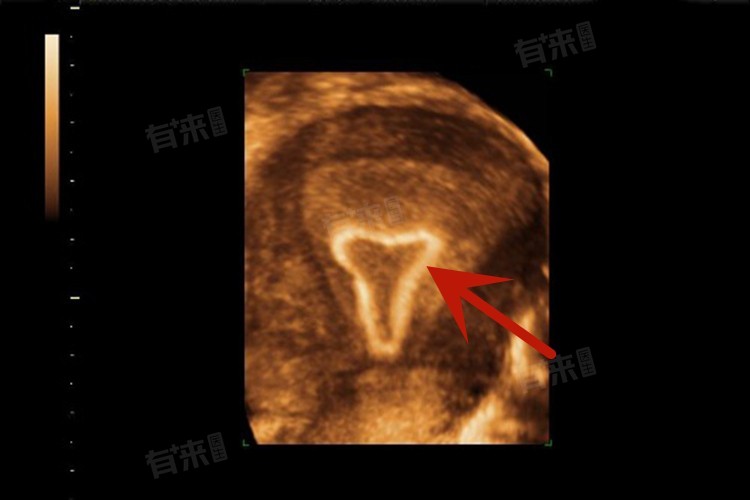

1、定期检查随访:放置曼月乐环后,按照医生要求定期进行妇科检查,包括B超检查等,监测环的位置是否正常,了解子宫内膜情况以及身体对环的适应状况,及时发现潜在问题。